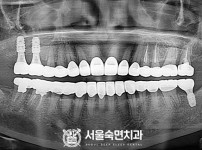

임플란트-전후사진1

치과를-선택할-때-꼭-확인하세요-서울숙면치과-임플란트-전후사진